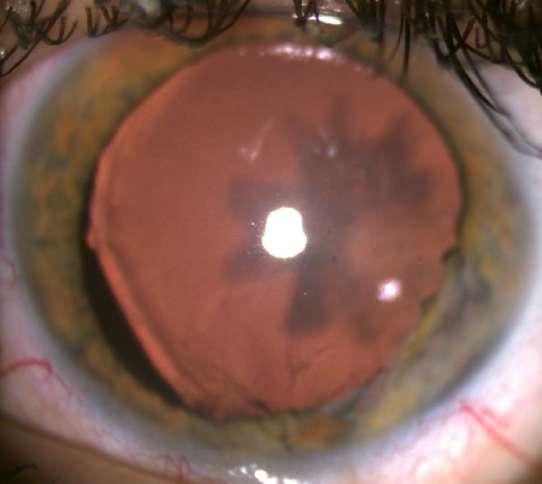

Caso aportado por Dr. Cristian Sanchez

Hombre 53 años con anteccedentes de facoemulsificación + implante de lente OD, consulta tras episodios de uveitis hipertensiva a repetición asociados a hifema del ojo derecho.

ü AV 0.7 OD

ü PIO OD: 28mmHg

ü BMC (Imagen A y B): Córna transparente, cámara anterior formada, Tyndall +, LIO in situ, transiluminación sectoriales del iris, iridotomías superior e inferior. Nevus conjuntival.

UVEÍTIS - GLAUCOMA - HIFEMA

8.C. SÍNDROME

A B

Caso

aportado por Dr. Cristian Sanchez

ü Gonioscopía (Imagen C): Ángulo abierto en en 270º, trabéculo con pigmento, SAP inferior

ü Fondo de ojo (Imagen D): Papila pálida con excavación 0.9. macula sana

ü El Sd. UGH es una complicación que puede aparecer en el post operatorio (precoz o tardío) luego de la implantación de un lente intraocular.

ü Se define clásicamente por la triada que su nombre comprende, aunque pueden aparecer formas incompletas.

ü La incidenccia se ha visto aumentada debido al incremento de la cirugía de cristalino, ya sea por catarata o con finalidad refractiva.

ü La patogenia se debe a la presión ejercida por los hápticos del lente intraocular (LIO) sobre el tejido uveal y puede presentarse en paciente con lentes en cámara anterior, sulcus o saco.

ü Sospechar en paciente pseudofáquico con episodios recurrentes de uveitis no filiada C D

8.C. SÍNDROME UVEÍTIS - GLAUCOMA - HIFEMA (UGH)

Sánchez C, Brosa H, Sanz S, Lillo J. Síndrome uveítis – glaucoma – Hipema: tres casos, tres causas. Hospital universitari de Bellvitge. Auditori Axa- Barcelona. 2016.